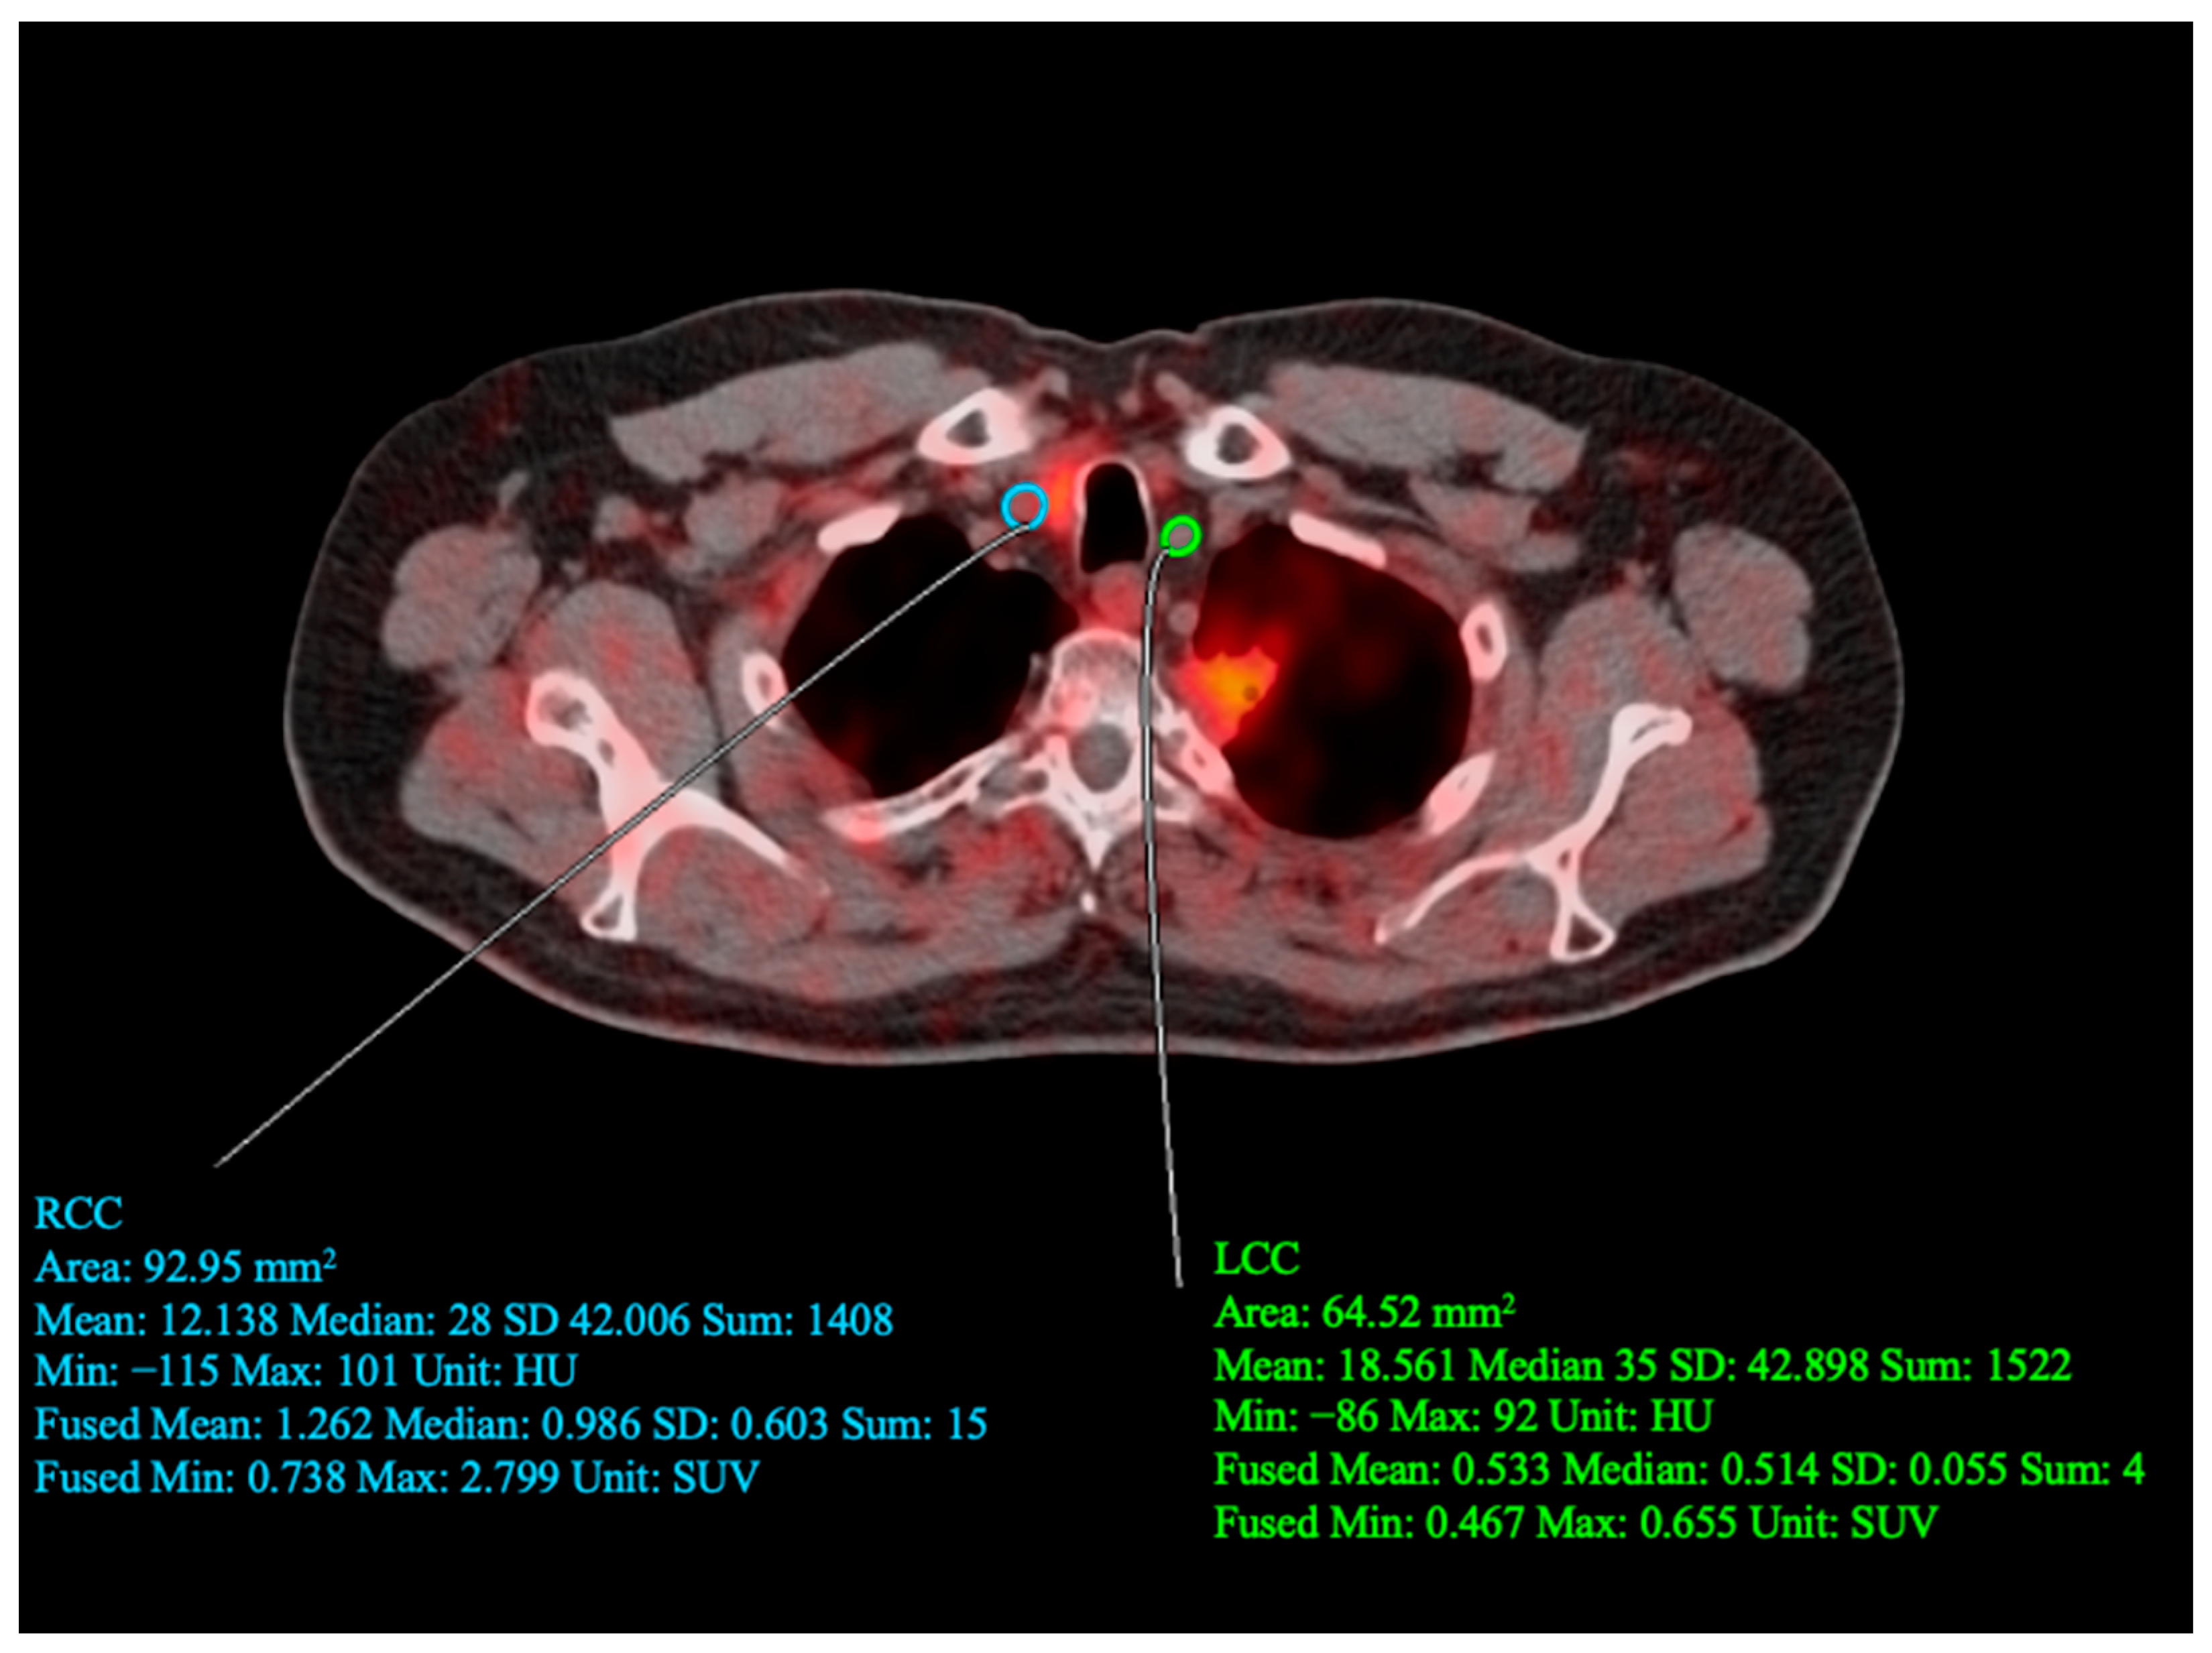

2.4. Carotid PET/CT Data Analysis

- Castro, S.A.; Muser, D.; Lee, H.; Hancin, E.C.; Borja, A.J.; Acosta, O.; Werner, T.J.; Thomassen, A.; Constantinescu, C.; Høilund-Carlsen, P.F.; et al. Carotid Artery Molecular Calcification Assessed by [18F] Fluoride PET/CT: Correlation with Cardiovascular and Thromboembolic Risk Factors. Eur. Radiol. 2021, 31, 8050–8059. [Google Scholar] [CrossRef] [PubMed]